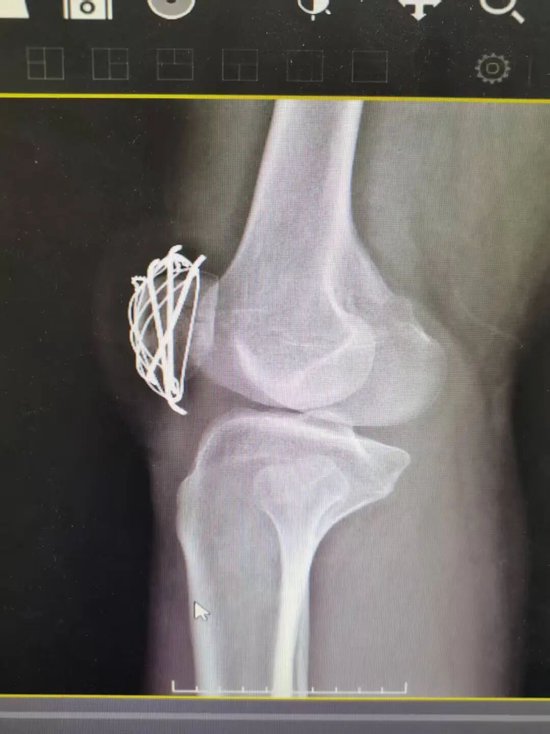

针对王先生病情,科室团队迅速制定周密手术方案,由杜明主任主刀,倪守洋医师协助,在硬膜外麻醉下为患者实施手术。术中探查发现,患者髌骨呈横形断裂且伴有碎骨,情况较为复杂。手术团队首先细致清理关节内血肿,随后在C臂透视机实时引导下,将骨折块进行精准对位,恢复关节面平整。随后,采用克氏针联合张力带钢丝进行内固定。该技术如同为骨折部位构建了一个坚固的 “内部脚手架” ,既能稳定骨折端,又能将分离的应力转化为促进愈合的压力,为骨骼愈合创造最优力学环境,最终实现骨折满意复位与可靠固定。